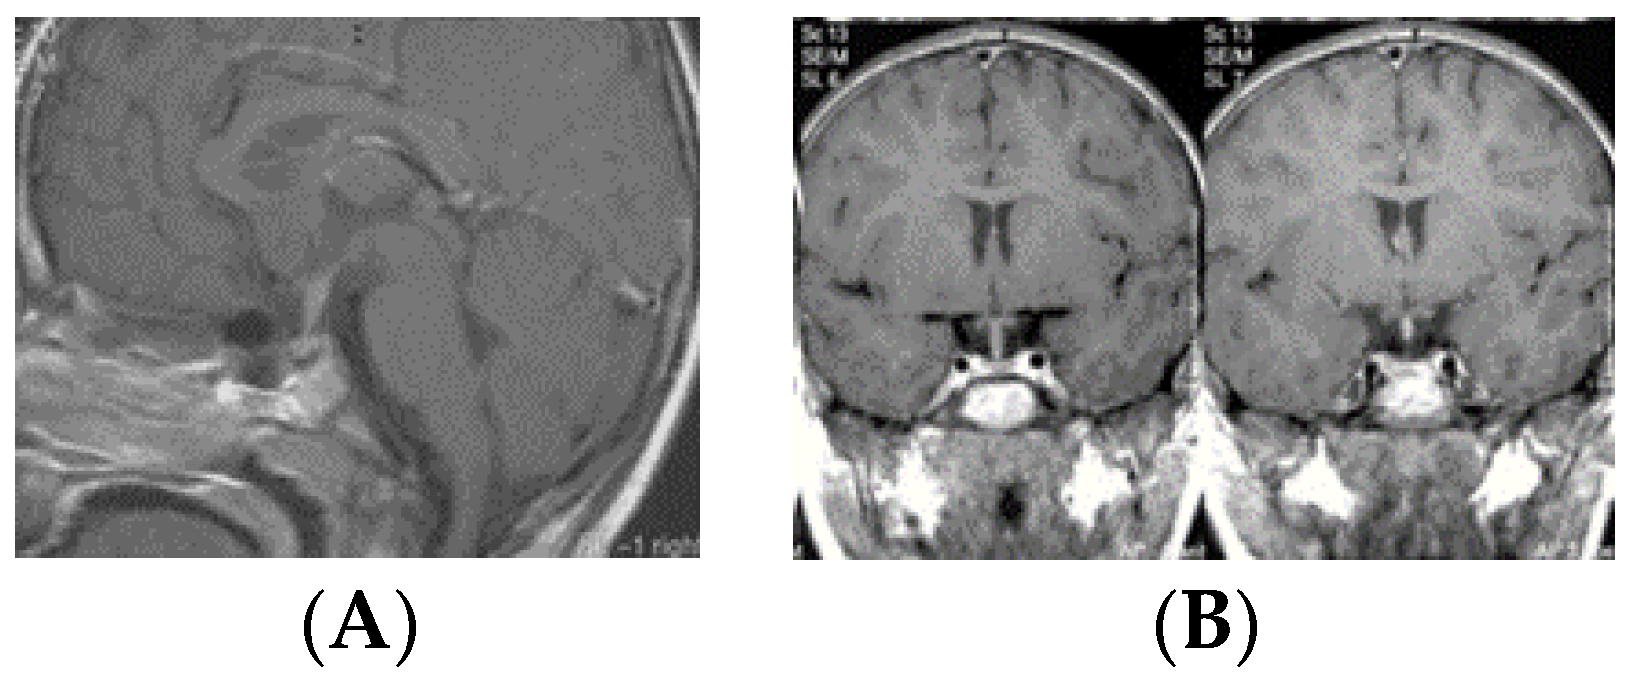

• Type IV: Small laminar (L) or nodular (N) lesion at the floor of III ventricle extending to upper PS (Figure 5);

Figure 5. Type IV. Post-contrast MR, sagittal (A) and coronal (B) views of a patient with bifocal germ cell tumor (GCT). Note a laminar tumor at the floor of the third ventricle with upper pituitary stalk involvement. Post-contrast MR, sagittal (C) and coronal (D) views of a patient with bifocal GCT with a nodular tumor at the floor of the third ventricle with upper pituitary stalk involvement.